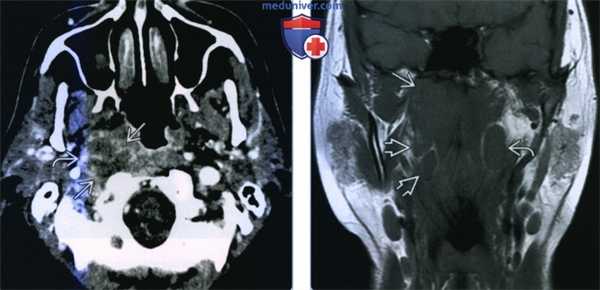

(Слева) КТ с КУ, аксиальная проекция. Пациент 63 лет, которому год назад проводилось хирургическое вмешательство и лучевая терапия по поводу ПКР ротоглотки. В левом отделе заглоточного пространства определяется метастаз в лимфоузел (рецидив). Имеется периферическое кольцо накопления контраста. Лимфоузел расположен медиальнее внутренней сонной артерии, которая, в свою очередь, сужена и частично включена в опухол.

(Справа) МРТ Т1ВИ, коронарная проекция. Пациент с новообразованием верхних отделов глотки. Рак носоглотки, локализующийся преимущественно в правой ее половине. Увеличены два заглоточных лимфоузла справа и один заглоточный лимфоузел слева.